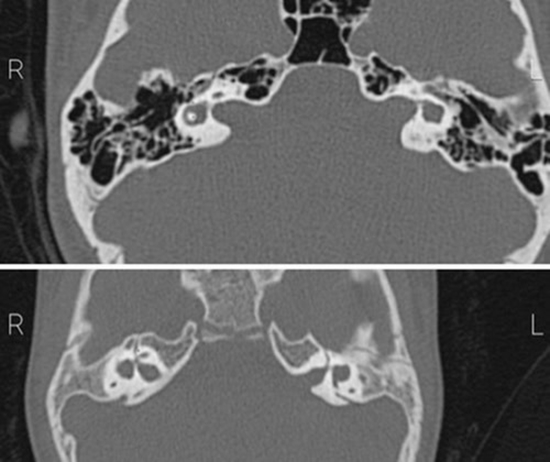

Correlation of CT Scan and Audiogram Findings in Ears with Lateral Semicircular Canal Dysplasia

Lateral semicircular canal (LSCC) dysplasia is a common malformation of the inner ear, which often results in hearing loss. The relationship between the extent of LSCC dysplasia and hearing loss severity is not well-understood. This case series aimed to investigate the differences in bony island radiologic measurements in patients with LSCC dysplasia according to hearing loss classification. Patients were recruited if they were less than 40 years old, underwent computed tomography scan (CTS) and had suspected LSCC dysplasia. The images were reviewed and the anterior-posterior diameter (APD), transverse diameter, and the surface area of the bony island were measured in millimeters. Audiometric data were used to classify hearing loss as profound hearing loss (PHL), conductive hearing loss (CHL), or mixed hearing loss (MHL). We also recorded patients’ demographics, and clinical symptoms such as vertigo and tinnitus. SPSS software was used for data analysis and a p value less than 0.05 was considered significant. Fourteen patients were recruited and the mean age of the participants was 20.4 ± 14.4 years. Bilateral LSCC dysplasia was detected in 12 patients, and unilateral dysplasia was observed in 2 patients (a total of 26 ears). CHL, MHL and PHL affected 13 (50%), 8 (31%), and 5 ears (19%), respectively. The mean APD was significantly smaller in MHL ears than in CHL ears (p = 0.03). Likewise, ears with MHL had smaller mean surface area than CHL ears, although the difference was not significant (p = 0.1). Vertigo or tinnitus was present in three patients. Unilateral and bilateral external auditory canal atresia was present in two patients, and one patient, respectively. We found that CHL was more common than profound hearing loss and MHL in patients with LSCC dysplasia. APD of bony island is a useful radiologic maker to distinguish between different types of hearing loss in this patient population. However, larger prospective studies are needed to confirm these findings and investigate the reasons for the observed smaller bony island in ears with MHL compared to those with CHL